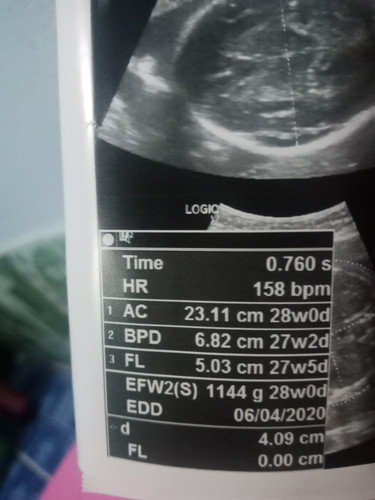

เเม่ๆ ตกลง ใบตรวจนี้ กี่วีคค่ะ. 27 หรือ 28.

อายุครรภ์จริงๆ คือตัวย่อ GA ค่ะ แต่ที่เห็นหลายๆวีคนั่นคือเทียบเท่า BPD = การวัดความกว้างของศีรษะทารก AC = การวัดเส้นรอบท้อง FL = การวัดความยาวกระดูกต้นขา EFW = การคะเนน้ำหนักทารกในครรภ์

28weekพอดีเป๊ะ =7เดือนจ้า

28 week พอดีค่ะ